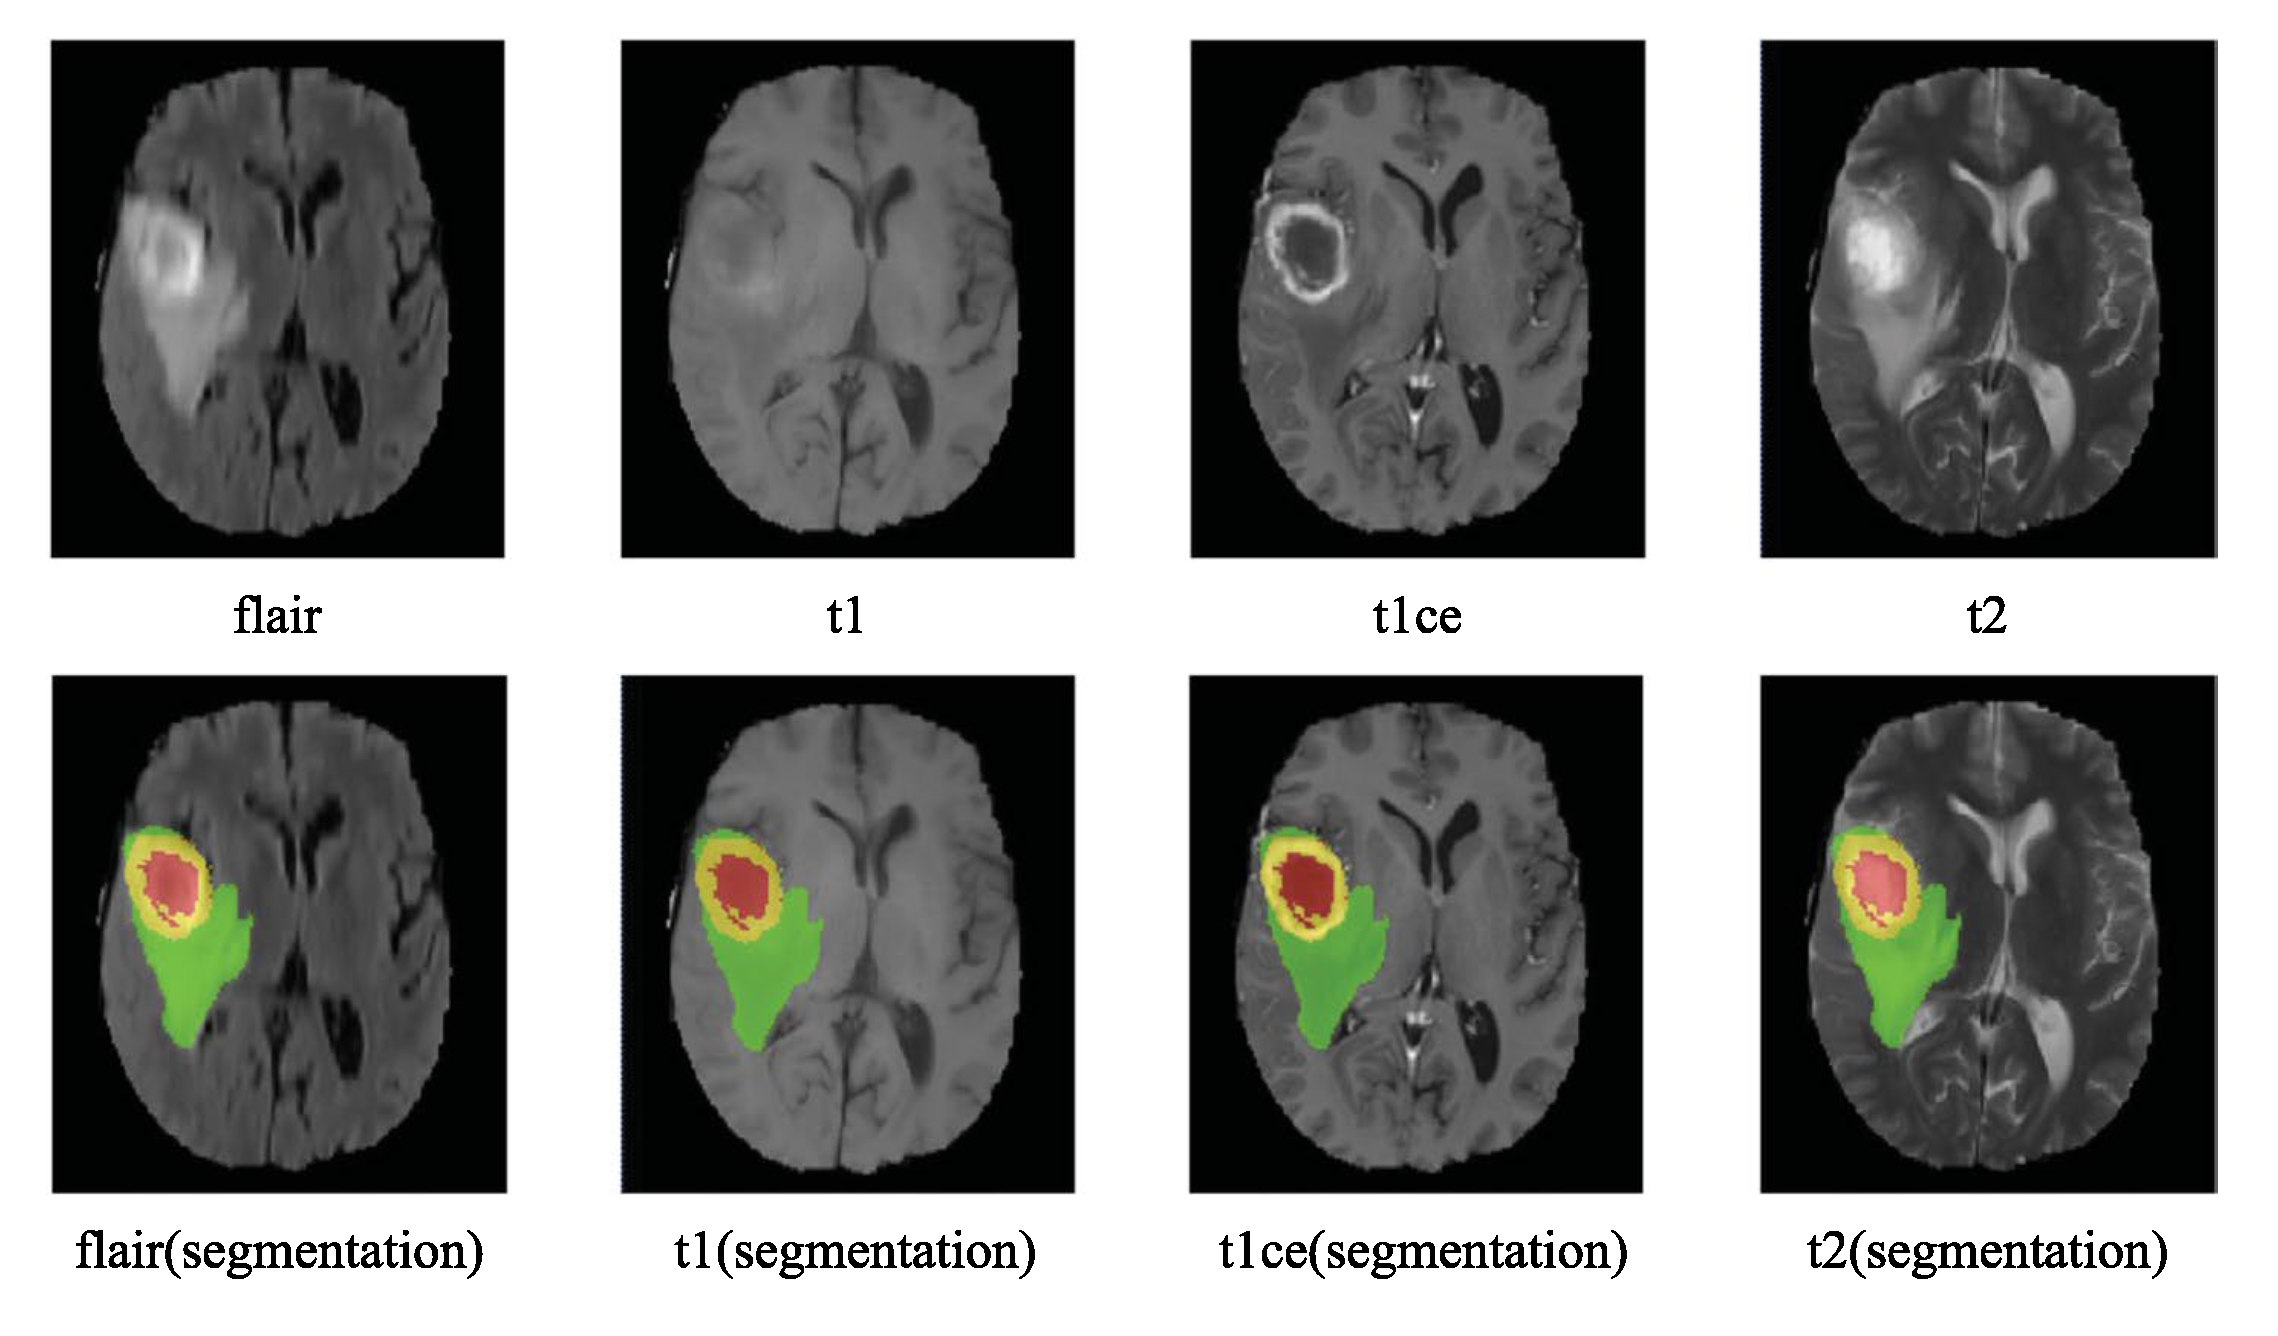

- label 1 — ED : edema;

- label 2 — TC : tumor core.

- label 1 — NCR : necrotic tumor;

- label 2 — ED : peritumoral edema;

- label 3 — NET : non-enhancing tumor;

- label 4 — ET: enhancing tumor;

- label 0 : everything else.

- Whole tumor region (WT): Includes all four tumor structures, corresponding to labels 1+2+3+4.

- Tumor core region (TC): Contains all tumor structures except for "edema", corresponding to labels 1+3+4.

- Enhancing tumor region (ET): Includes only the "enhancing core" structures that are unique to high-grade cases, corresponding to label 4.

- "edema" was primarily segmented from T2-weighted images. FLAIR sequences were used to verify the extent of the edema and to differentiate it from ventricles and other fluid-filled structures. Initial segmentation in T2 and FLAIR included the core structures, which were then reclassified in subsequent steps.

- The gross tumor core, encompassing both enhancing and non-enhancing structures, was initially segmented by assessing hyper-intensities on T1c images (for high-grade tumors) along with inhomogeneous components of the hyper-intense lesion evident in T1 and the hypo-intense areas seen in T1.

- The “enhancing core” of the tumor was subsequently segmented by thresholding T1c intensities within the resulting gross tumor core. This segmentation included the Gadolinium-enhancing tumor rim while excluding the necrotic center and blood vessels. The intensity threshold for segmentation was determined visually for each case.

- The "necrotic (or fluid-filled) core" was identified as irregular, low-intensity necrotic areas within the enhancing rim on T1c images. This label was also applied to the occasional hemorrhages observed in the BRATS dataset.

- The "non-enhancing (solid) core" was characterized as the part of the gross tumor core remaining after the exclusion of the "Enhancing core" and the "necrotic (or fluid-filled) core."